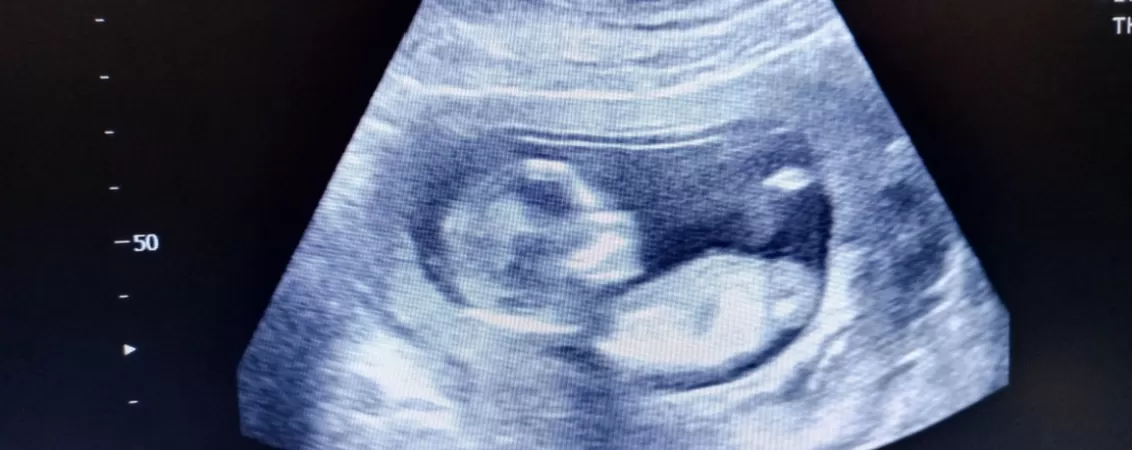

În plus, prin efectuarea unei ecografii la 15 săptămâni de sarcină se măsoară nivelurile anumitor proteine și hormoni din sângele mamei, pentru a evalua riscurile ca bebelușul să dezvolte defecte ale tubului neural și anomalii cromozomiale.